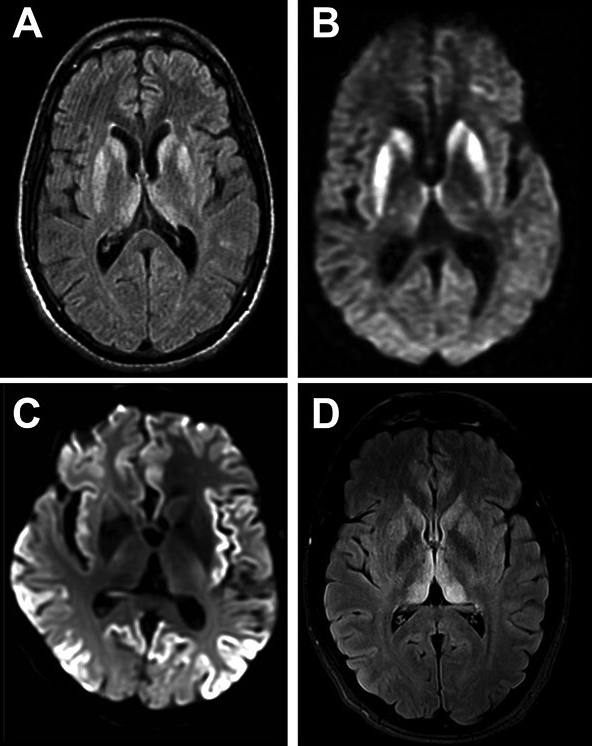

CreutzfeldtJakob Disease Comparative Analysis of MR Imaging Sequences Creutzfeldt-Jakob Disease Lp learn about the evolution of diagnostic techniques for cjd, a rare and fatal neurologic disorder caused by prions. Learn about the types, causes,. cjd is a rare, fatal brain disease caused by prions, which are faulty proteins that damage brain cells. Creutzfeldt-Jakob Disease Lp.